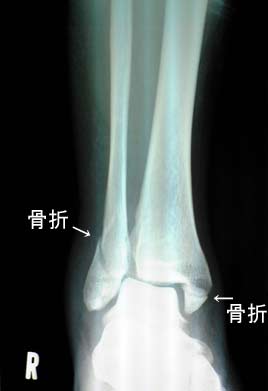

やっと当初の骨折レントゲン写真を撮らせていただきました。懐かしく痛々しそうですが、あまり骨折の痛みは感じていなかったです。これが正面から移したレントゲン写真です。正面から見た内側(写真の右側)は、下側小さく折れている様子です。外側(写真の左側)は、鋭く折れているのですが、この写真ではちょっと不明。下側の骨も曲がってしまっているそうですが、素人には判りませんね(笑)この写真は足を外側に広げて取った物です。これだと最初の写真の内側の部分が、ぽっきりと折れて外れているのが判ります。この写真は足の内側を下にして撮った物です。これだと最初の写真の外側の部分が鋭く折れて外れているのが判ります。これが筋肉を傷つけていたらもっと痛かったと思われます。これが現在の状況です。リハビリも順調なので今まで通りのリハビリを自宅で行って良いと言うことです。ほんまにええのか?二足歩行もしょっちゅうしてるで?では、今まで通りゆっくりと順調に自主リハビリ頑張ります(笑)